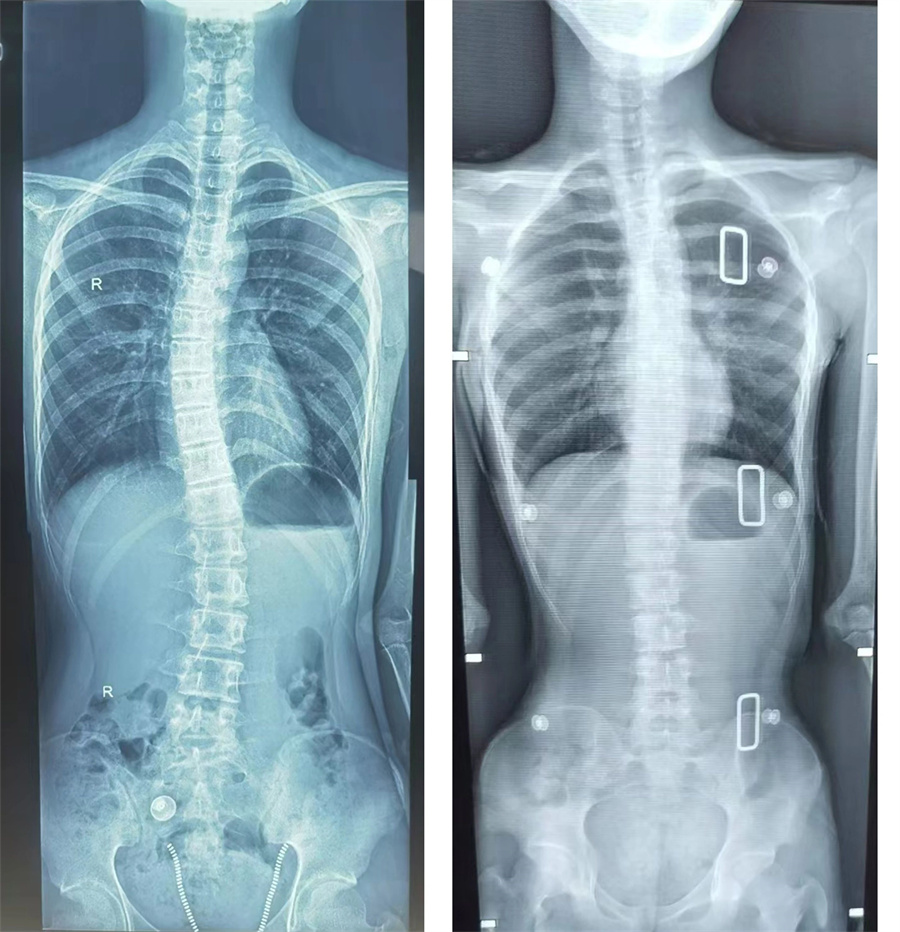

简单查体时,少年就暴露出明显的双肩不等高,弯腰做触地动作时,背部双侧不对称。X光片数据最终也证实了医生的判断:胸腰椎侧弯已达27度,相当于脊柱中段偏移了4.5厘米!“这就像正在生长的树苗突然被风吹歪了。”高凤奇主任用形象的比喻向家长解释,“好在发现及时,现在正是矫正黄金期。”

考虑到患儿骨骼尚未成熟,且侧弯角度处于20-40度的保守治疗窗口期,高凤奇主任决定对其采取支具保护的方式进行治疗。高凤奇主任介绍,孩子侧弯角度虽大于20度,但庆幸的是,脊柱不是先天性发育畸形,二是特发性的青少年脊柱侧弯。支具治疗就像给脊柱穿上隐形矫正衣,只要坚持规范佩戴一到二年,同时配合核心肌群训练,预计可将侧弯角度控制在安全范围内。